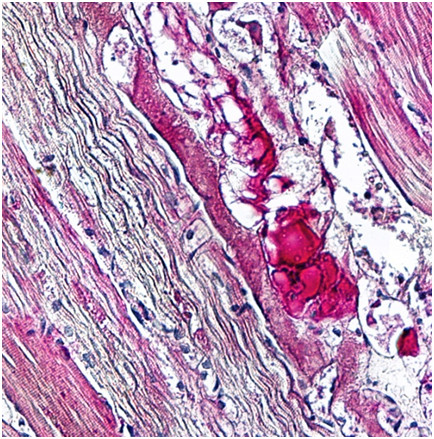

Na przekroju przez półkule mózgu widoczny jest: